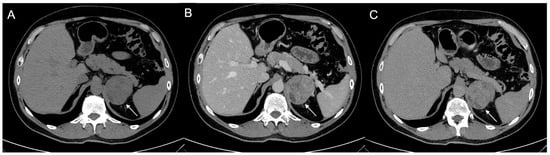

Figure 8.

79-year-old female patient with left adrenal lesion detected at abdominal ultrasound performed for abdominal pain. Homogeneous left adrenal mass with density on non-contrast CT (A) less than 10 HU (6 HU, SD4 HU) and washout (>60%) in the venous (B) and late post-contrast phases (C), compatible with adenoma.